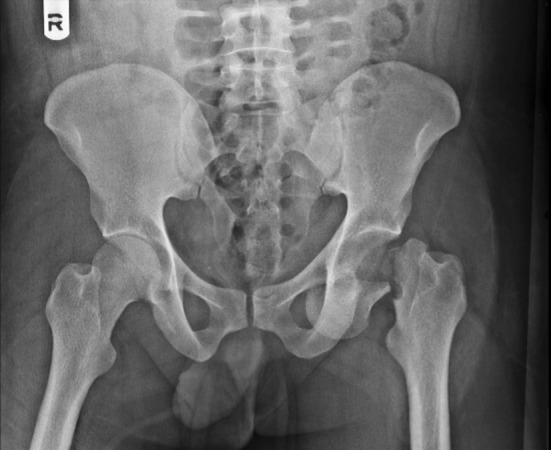

The X-rays revealed a fracture of the left clavicle, a comminuted fracture of the left scapula and a fracture of the neck of the left femur with anterior dislocation of the femoral head (obturator type) (Fig. 1).

Fig. 1.

X-ray pelvis AP showing fracture neck femur with obturator-type anterior dislocation